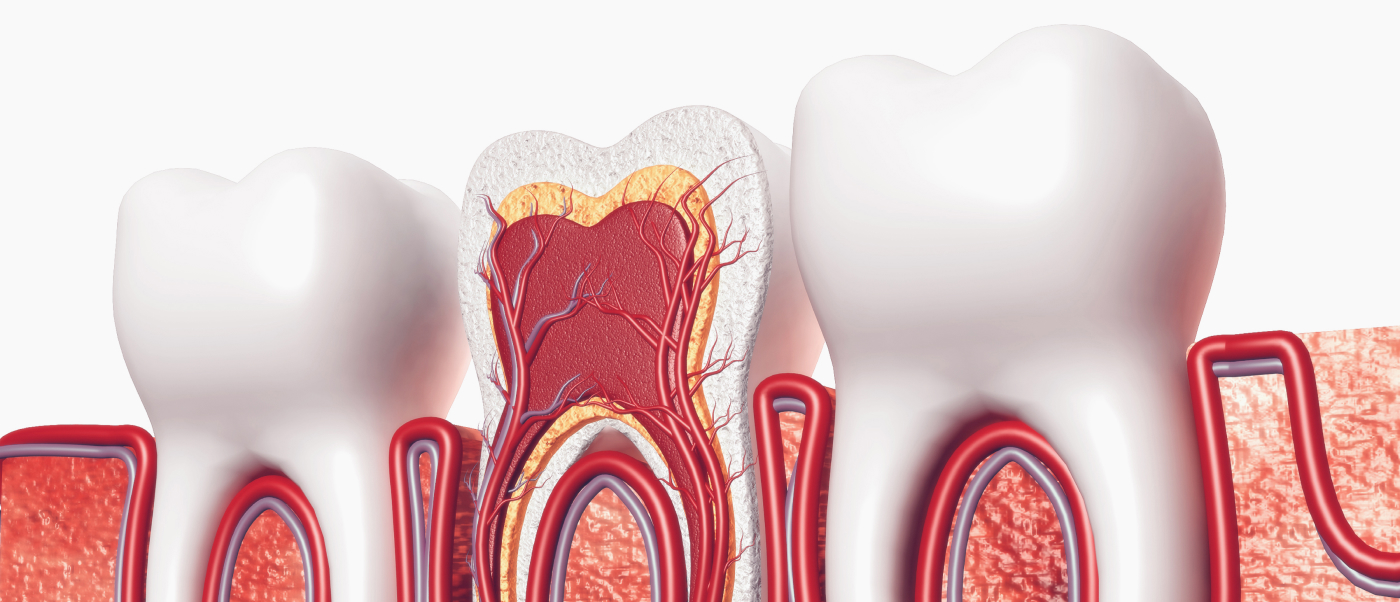

신경(근관) 진행과정

• 01 초기 충치(법랑질 우식)

통증은 거의 없지만, 미리 예방 처치를 진행하면 치아를 온전히 보존할 수 있습니다.

• 02 진행 충치(상아질 우식)

시림이나 자극 후 통증이 나타납니다. 빠른 치료가 필요합니다.

• 03 신경 염증(치수염)

충치가 치수에 도달해 자발통·야간통이 생기므로, 염증 치수를 제거하는 신경치료가 권장됩니다.

• 04 치근단염

신경이 괴사하면서 뿌리 끝에 염증과 고름이 형성되어 발치할 수 밖에 없는 상황으로 이어질 수 있습니다.